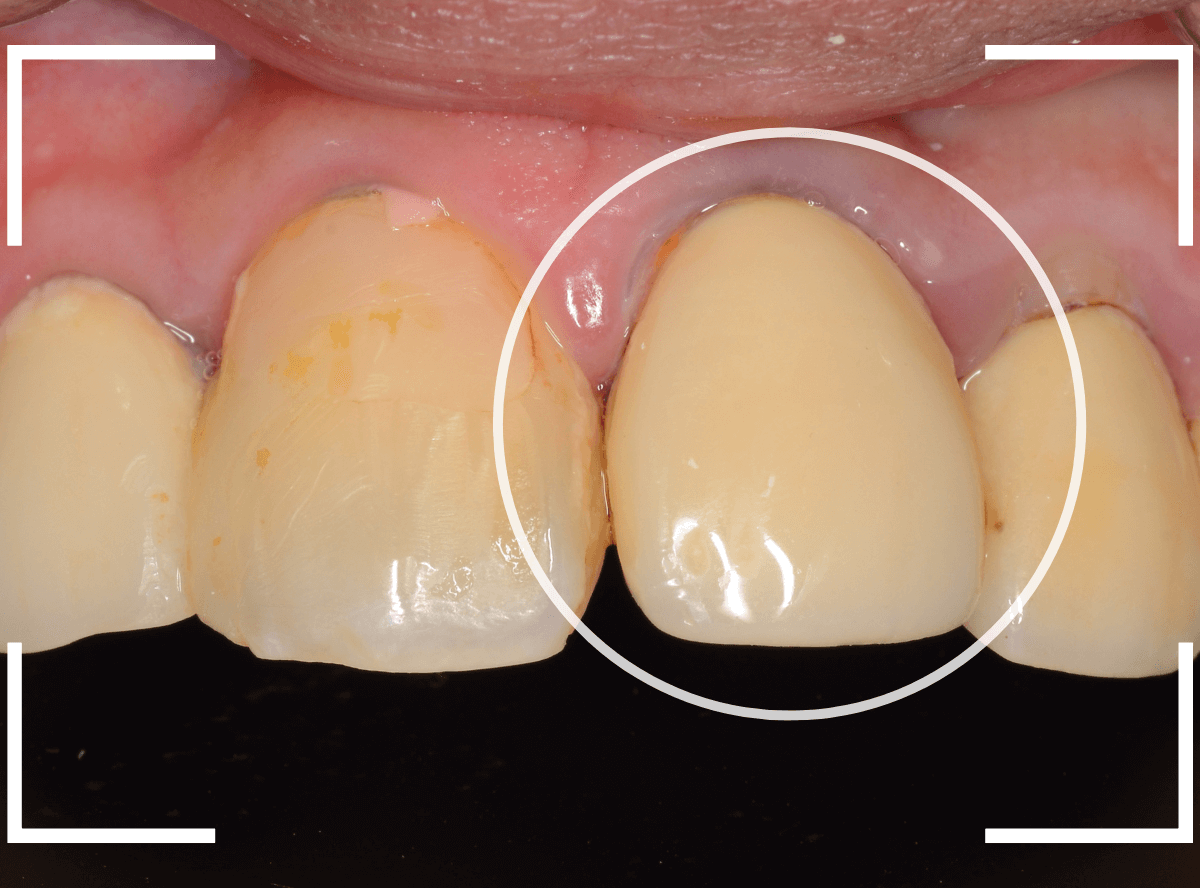

Case.5

さし歯の周りを歯石除去すると、血まみれになるのは何故?

今回は、さし歯の周りの歯周治療についてです。

〇部の前歯のさし歯ですが、隣の歯との形が不釣り合いな感じはありますが、見た感じそんなに問題はなさそうです。

しかし、さし歯の周りを軽く歯石除去をすると、たちどころに血まみれになってしまいます。

いったい何故でしょうか?

レントゲン写真で確認します。

隣のさし歯も、ですが、さし歯の縁が見えないところで不適合になっています。

これでは、いくら歯ブラシを頑張っても、汚れがたまってしまい、歯肉の改善ができません。

歯肉にぴったりあったさし歯に作り直す必要があります。

どの程度の不適合でさし歯を作り直すか、は状況によって判断は別れます。